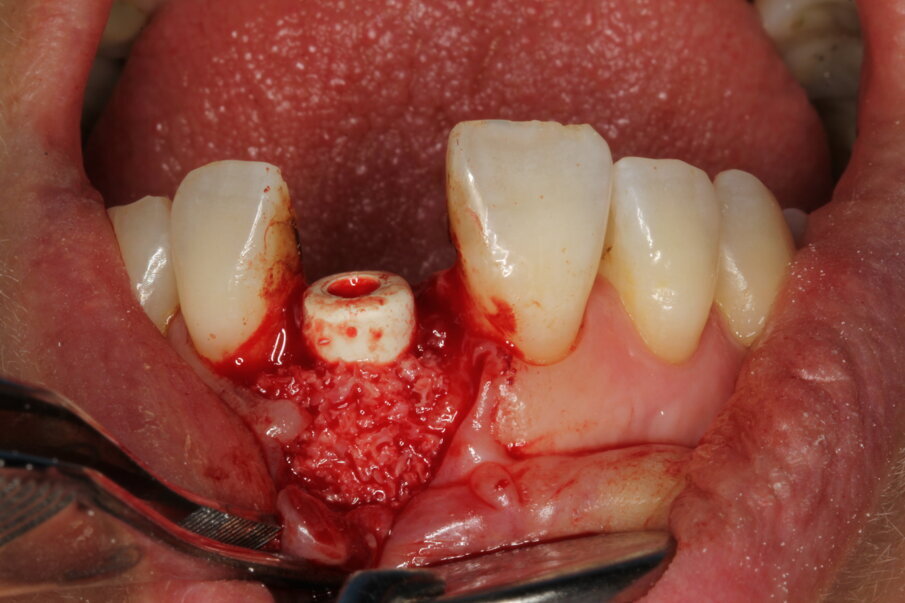

Local anaesthesia was performed with 2% mepivacaine with 1:100,000 adrenaline. Preventative antibiotic therapy with amoxicillin (1 g, b.d. for five days) was prescribed, aided by use of a 0.2 % chlorhexidine mouthrinse three times a day for one minute. The tooth was extracted and the sulcular epithelium removed with diamond burs. The milled surgical template (Figs. 12 & 13) served as a guide for the first 2 mm diameter pilot drill (Fig. 14). Thus, the planned depth, position and angulation of the osteotomy were obtained. The drill sequence was completed freehand, using tapered 3.0 and 3.4 mm drills. A Neoss Pro- Active Tapered Implant of 4 mm in diameter and 13 mm in length was inserted flush with the mesial/palatal/distal bone, motor driven up to a torque of 50 Ncm and then with a manual wrench (Fig. 15). The correct position of the internal hex was verified by checking the references on the implant driver, which ideally points in the buccal direction. Resonance frequency analysis with Penguin RFA (Integration Diagnostics Sweden) determined an ISQ value of 73/76. At this stage, a Neoss Esthetic Healing Abutment with a ScanPeg was connected to the implant (Fig. 16). A flap was then raised after a vertical incision of the frenulum and the expected buccal exposure of the implant neck was evident. Autogenous bone harvested from the drills was positioned directly on the implant surface (Fig. 17), followed by a bone substitute on top of it and on the buccal cortical bone (Fig. 18). This material was covered with a resorbable membrane (Fig. 19). The mobilised flap was then repositioned by rotating it coronally and fixed with single sutures (Fig. 20). The removable partial denture was adapted and delivered (Fig. 21). An immediate postoperative CBCT scan of 60 x 60 mm was performed, and it confirmed a perfectly centred implant position (Figs. 22 & 23).